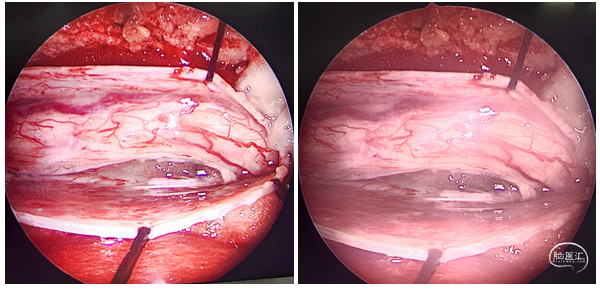

图3 手术过程: 肿瘤完全位于脊髓及神经根腹侧,脊髓受压严重,整块切除肿瘤,受压脊髓已有变性改变等。

陈卓鹏医师在电生理监测及内镜中的协助为手术的顺利完成提供了帮助。分离肿瘤与神经根及脊髓的界面,脊髓受压超过90%,受压处两端脊髓已有变性改变。术后患者下肢麻木感及肌力稳步改善。